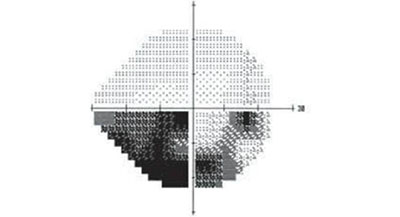

青光眼患者的眼睛同時(shí)存在這兩個(gè)特征:視神經(jīng)萎縮,和視野損害。如圖所示,視神經(jīng)是中樞神經(jīng)系統(tǒng)的一部分,也是把視覺信息傳送到大腦視中樞的傳導(dǎo)路徑的起點(diǎn)。

視野指的則是眼睛看向正前方時(shí)所能看到的空間范圍。在檢查中,視野常被劃分為四個(gè)象限,下圖就是一位青光眼患者的視野檢查結(jié)果,圖中黑色部分為視野缺損的部分。